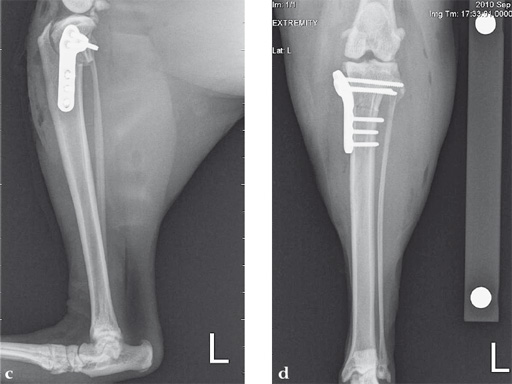

Case 2: Cat

(Case provided by Brian Beale, Houston, USA)

A 10-year-old female, spayed, 6.0 kg cat had a partial tear of the left cranial cruciate ligament, meniscal mineralization, and a medial meniscal tear. The cat was treated with a partial meniscectomy and TPLO . A 2.0 mm TPLO plate was perfect for this cat due to the slope of the tibial plateau (25) and the size of the cat. Three 2.0 mm locking screws were used proximally and three 2.0 mm cortex screws were used distally. The contour of this plate does not perfectly match the contour of the proximal tibia, but use of locking screws in this segment avoids any potential angulation of the segments as the screws are tightened. The cat healed uneventfully and returned to normal function.